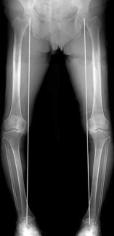

変形性膝関節症

人工膝関節全置換術後